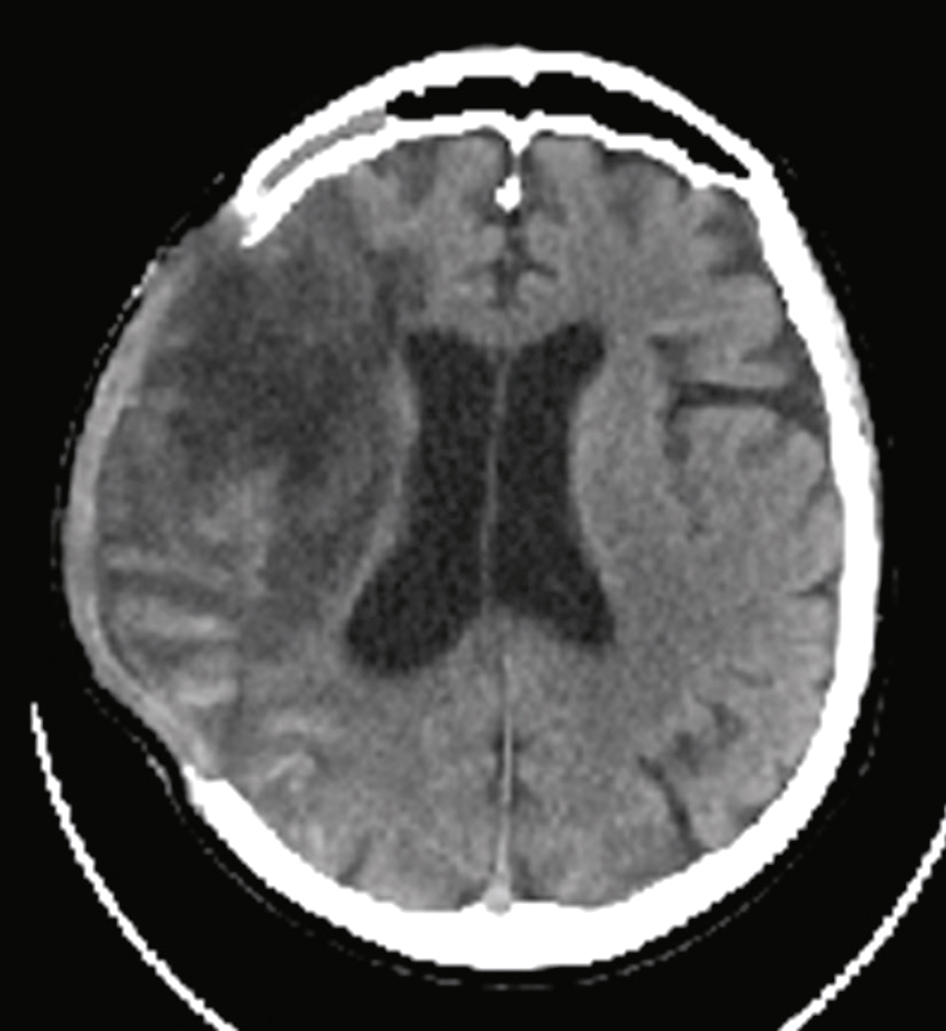

Figure Contenu multimédia Exemple d’AVC ischémique en phase aiguë en TDM

Fig. 28.13 Figure Signes précoces d’ischémie cérébrale en scanner sans injection.

A. Scanner cérébral normal. B. Hypodensité systématisée au territoire sylvien, effacement partiel du noyau lenticulaire et effacement des sillons corticaux hémisphériques droit (flèche bleue). C. Hyperdensité spontanée de l’artère cérébrale moyenne droite (signe de la sylvienne blanche ou « trop belle artère » – flèche rouge).

Les images de TDM montrent des signes précoces d'ischémie cérébrale : perte de différenciation entre la substance grise et blanche, et hypodensité dans le territoire cérébral.Les signes précoces d’ischémie cérébrale en scanner sans injection peuvent être identifiés par plusieurs caractéristiques visibles sur les images de tomodensitométrie (TDM). L’ischémie cérébrale est une condition où le flux sanguin vers une partie du cerveau est réduit, entraînant un manque d'oxygène et de nutriments nécessaires au bon fonctionnement des cellules cérébrales. Sur l'image A, on observe une coupe axiale d'un scanner cérébral sans injection de produit de contraste. Cette image montre une densité normale des tissus cérébraux sans signes évidents d'ischémie. L'image B présente également une coupe axiale d'un scanner cérébral sans injection. Un signe précoce d’ischémie cérébrale visible ici est la perte de différenciation entre la substance grise et la substance blanche, indiquée par une flèche bleue. Cette perte de différenciation est due à l'œdème cytotoxique qui se produit lorsque les cellules cérébrales commencent à gonfler en raison du manque d'oxygène. L'image C montre une autre coupe axiale d'un scanner cérébral sans injection. Un autre signe précoce d’ischémie cérébrale est la présence d'une hypodensité dans le territoire de l'artère cérébrale moyenne, indiquée par une flèche rouge. Cette hypodensité représente une zone de tissu cérébral qui a une densité plus faible que le tissu environnant, suggérant une réduction du flux sanguin et un début de nécrose cellulaire. Ces signes précoces d’ischémie cérébrale sont cruciaux pour un diagnostic rapide et précis, permettant une intervention médicale appropriée pour minimiser les dommages cérébraux et améliorer les chances de récupération du patient.

2 Scanner sans injection

a Dans les premières heures

Il présente les caractéristiques suivantes :

• • en cas d’infarctus cérébral :

• – souvent normal,

• Figure signes précoces possibles (fig. 28.13) :

• – effacement des sillons corticaux,

• – dédifférenciation substance blanche/substance grise : atténuation du manteau cortical de l’insula, atténuation du noyau lenticulaire,

• – hyperdensité artérielle (artère sylvienne « trop belle ») témoignant du thrombus dans l’artère;

• Figure en cas d’hémorragie intraparenchymateuse : hyperdensité spontanée dont on précisera la localisation lobaire ou profonde.

b Au-delà de la 6e heure

• • L’hypodensité de l’infarctus cérébral apparaît et s’accentue les premiers jours :

• Figure elle est systématisée au territoire artériel infarci (fig. 28.13);

• – elle entraîne, après plusieurs mois, une dilatation du ventricule en regard et une atrophie localisée du parenchyme.